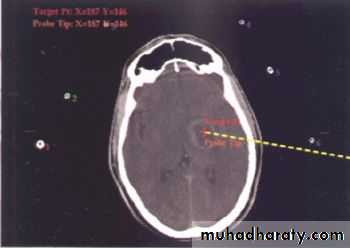

Stereotactic Aspiration of Brain Abscess

Neurosurgery